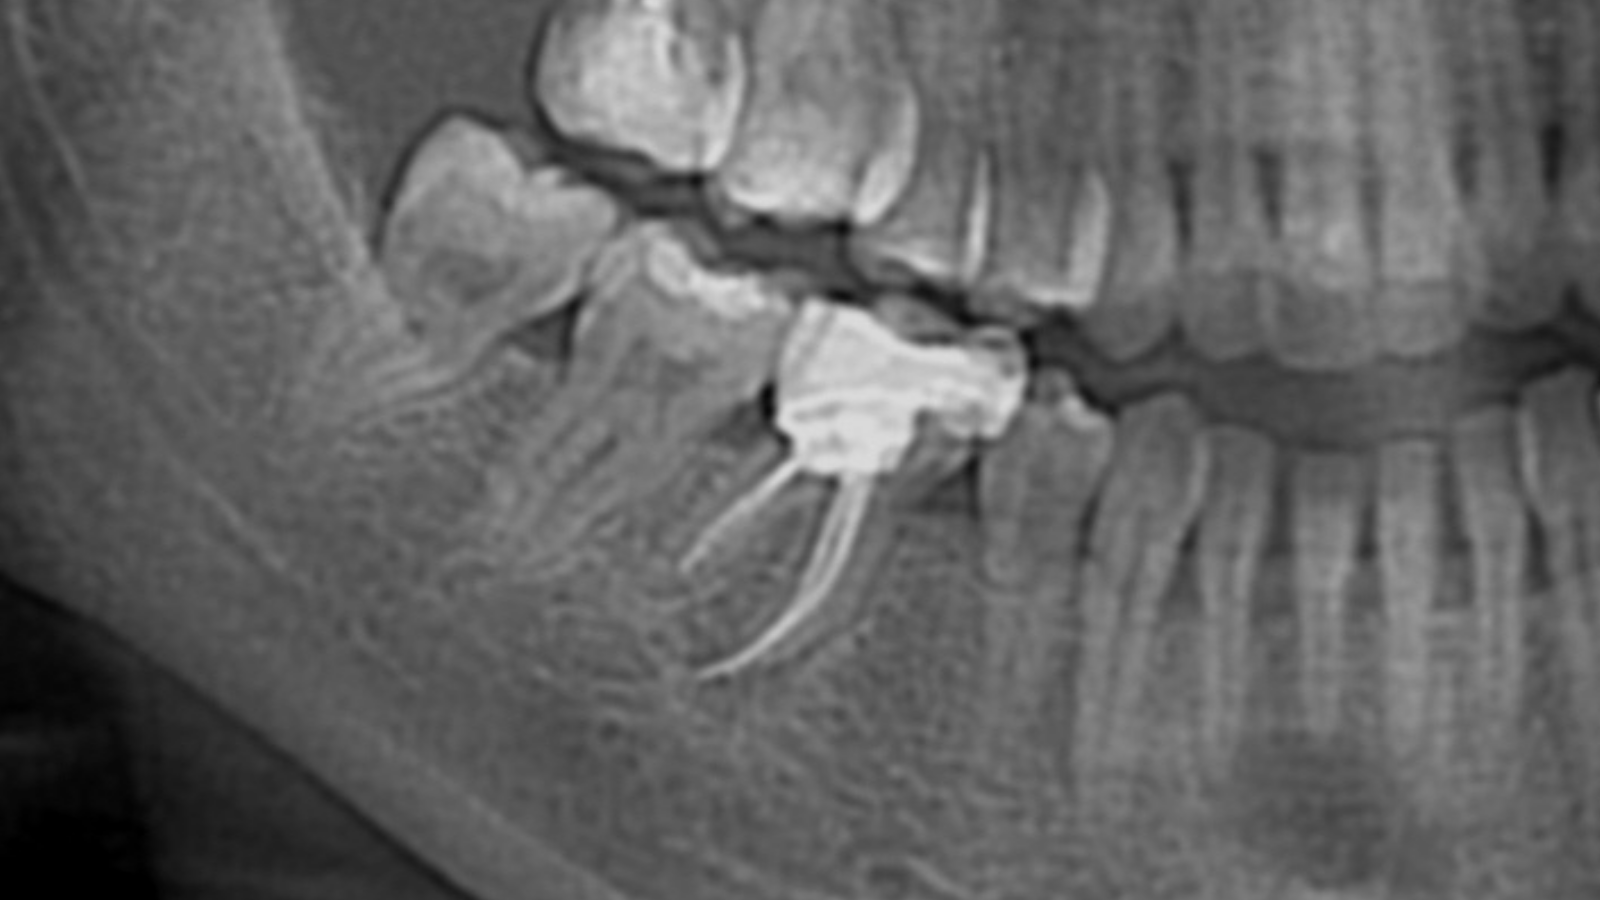

46 : infection périapicale, extraction–implantation immédiate avec greffe et membrane

Une patiente se présente au cabinet pour une infection périapicale au niveau de la 46, responsable d’une situation inflammatoire persistante. Après évaluation, la reprise du traitement canalaire s’avère impossible.

La prise en charge retenue a donc été chirurgicale : extraction de la dent, suivie d’une implantation immédiate. Afin d’optimiser les conditions de cicatrisation et de stabiliser le site, une greffe osseuse a été réalisée et recouverte par une membrane.

Cette approche permet de traiter l’infection, de préserver au mieux le volume osseux et de préparer une réhabilitation implantaire dans de bonnes conditions.